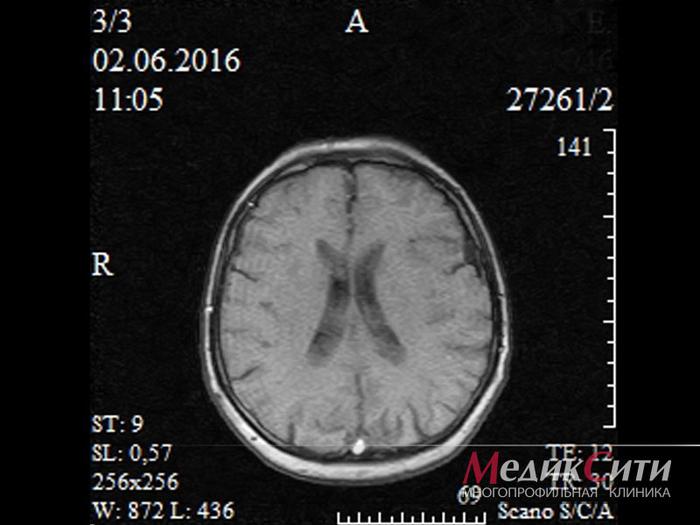

- МРТ или КТ, если нужна более детальная визуализация;